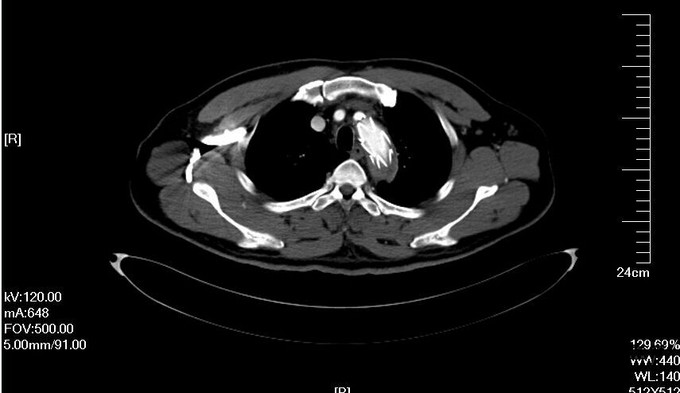

入院查体:体温36.5℃,脉搏90次/分,规则,呼吸18次/分,规则,血压150/80mmHg,胸廓正常,无胸骨叩痛。呼吸运动正常,语颤正常,无胸膜摩擦感,无皮下捻发感,叩诊正常清音,肺下界正常,双肺呼吸音粗,呼吸音对称,无罗音。心音可,心率90次/分,无杂音,腹部无压痛,无反跳痛,肝肋下未及,胆囊无压痛,Murphy征阴性,脾肋下未及,肾区无叩痛,双下肢不肿。入院后完善相关检查(胸腹主动脉CTA:主动脉夹层动脉瘤;两侧胸腔少量积液。)

予以诊断:1.主动脉夹层动脉瘤;2.高血压3级,极高危组。诊断明确后行“左颈总动脉-腋动脉转流手术+胸主动脉覆膜支架腔内隔绝术”。左侧颈部切口,游离出左侧颈总动脉,左侧锁骨下动脉,左侧椎动脉等分支。使用8mmG-tex血管一端与左锁骨下动脉行端侧吻合,G-tex血管另一端与左侧颈总动脉行端侧吻合。经右侧股动脉入路造影见主动脉夹层,破口位于左锁骨下动脉开口医院0.5cm处。左锁骨下动脉近端封闭,桥血管通畅,腋动脉及左侧椎动脉血流良好。置入美敦力胸主动脉覆膜支架(28*157mm),定位后释放。造影见胸主动脉支架释放良好。

主动脉夹层为大血管急诊,B型主动脉夹层相对预后良好。保守治疗效果尚可,近期死亡率相对不高。但对于年轻患者,我们积极治疗。患者B型主动脉夹层,破口位于锁骨下动脉附近。拟行腔内修复术。但患者破口离锁骨下动脉较近,若直接封闭,可影响左上肢活动及椎动脉顺行血流。故根据患者情况行一期复合手术(即“左颈总动脉-腋动脉转流手术+胸主动脉覆膜支架腔内隔绝术”)。术后复查可及左侧锁骨下动脉通畅,血流灌注可。可及假腔内明显血栓化。